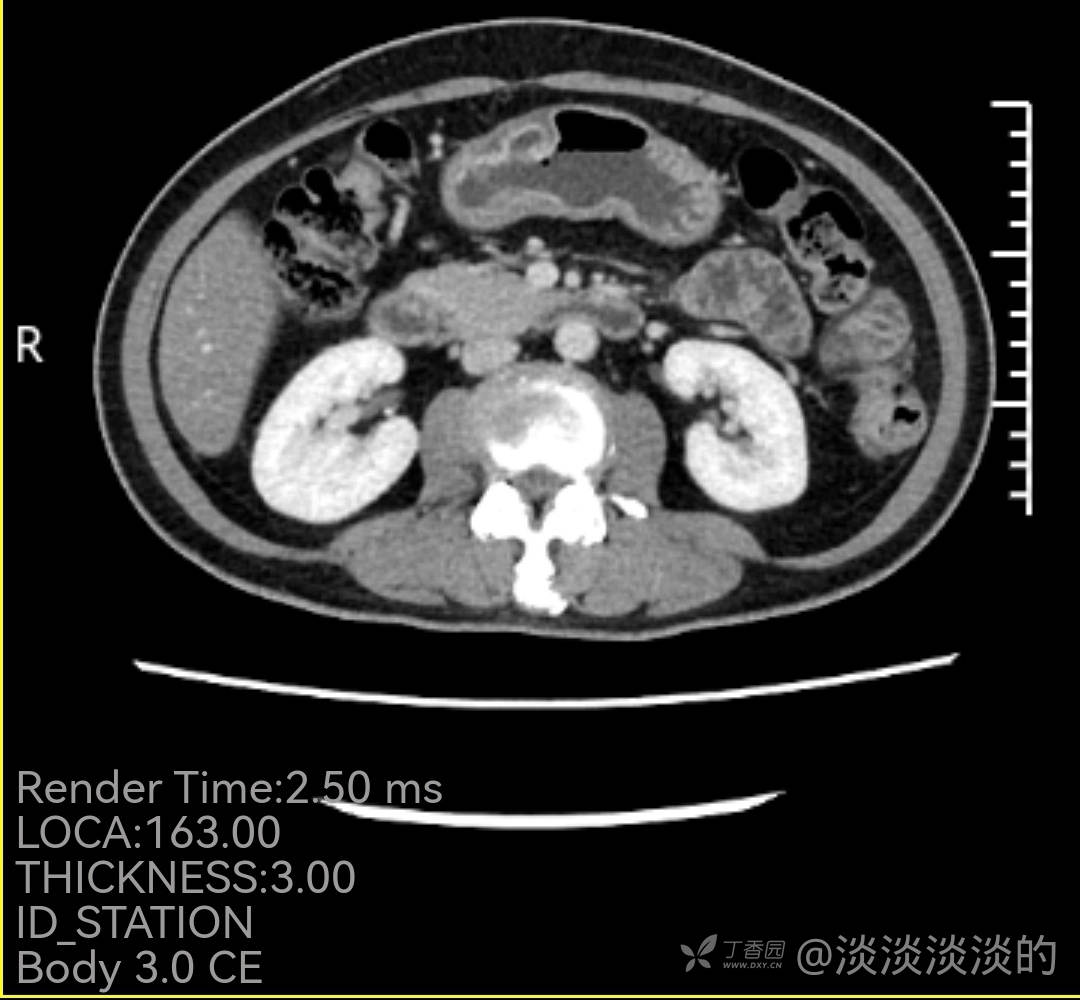

60岁女性,18年胃镜检查提示慢性胃炎,此次因上腹痛1月就诊,门诊检查发现胃窦前壁近胃角一病变,内镜,病理,增强CT如下,常规化验血检查没有明显异常,因病理良性,复查胃镜见最后1张,活检报告未出。